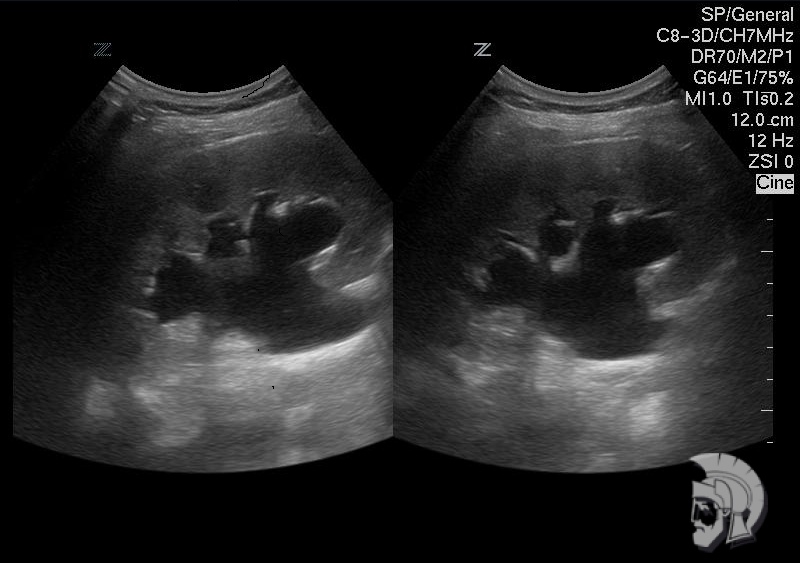

Фото почки.

Выраженная пиелоэктазия. Расширение чашечно-лоханочной системы левой почки мужчины 24 лет |